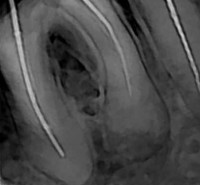

K03.4 Гиперцементоз